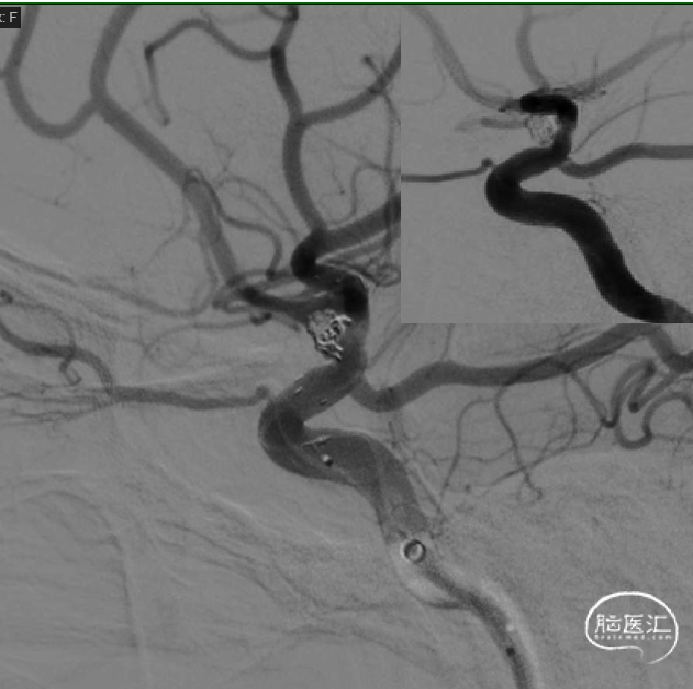

术后即刻工作位造影显示,支架全程打开形态良好,充分贴壁。

术后即刻正/侧位造影显示:各分支血管血流通畅,无出血情况,瘤体内无造影剂充盈。

术后3D造影:支架打开充分,全程贴壁,各分支血管血流通畅,可看到内翻的Mark点也被Evolve贴到了血管壁上,充分体现了Evolve足够强的径向力,预示着Evolve对动脉瘤合并狭窄应用或许是一个不错的选择。